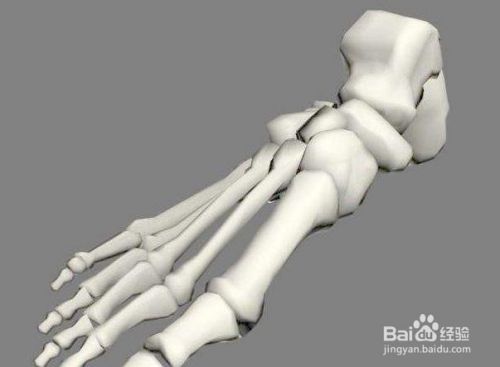

这个代夫家里的确没有门脸,就是在自己家里,有个黑黑的屋子里面还有陈旧的设备,用来拍片子的,要不是乡亲还真怕是上当受骗,简单了解了情况之后,又拍了个片子,他说你这骨伤只少得七八年以上了,怎么现在才来看,骨缝里都长上肉了,可不人家要给你开刀,骨头的端面都已经坏死了,长不到一起了,这个到你老了,弄好就残废了;